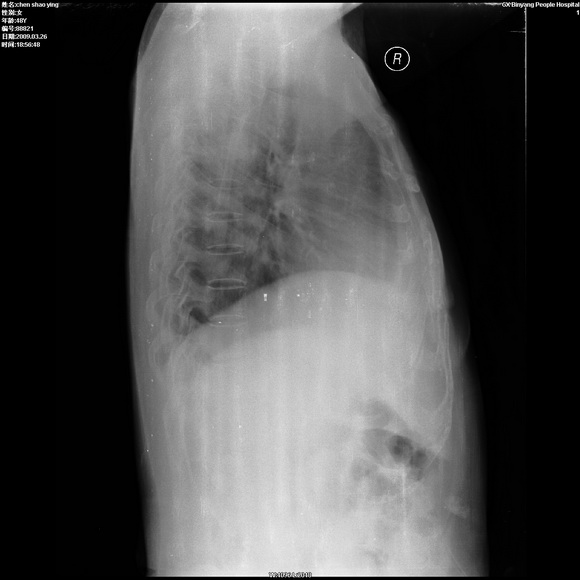

患者,女,48岁,发热伴陈发性咳嗽5天,偶尔痰中带血。体温约38°~40°;白细胞明显减低0.85x10的9次方/升。入院后抗炎、抗痨一周复查病灶明显进展。

右上肺后段实变影,内见支气管气象,肺门未见软组织肿块,气管前方有肿大淋巴结。左下肺见多个类圆形结节影。考虑:1.右上肺后段大叶性肺炎,需进一步检查病原体种类,应多询问病史,条件许可考虑做纤支镜检查2.左下肺结节影性质待定

考虑右上肺后段大叶性肺炎不除外结核,伴双肺结节播散灶,希定期复查。

问题是抗炎治疗一个星期后病灶进展。

右肺于酪性肺炎并左肺播散。

考虑两肺继发性肺结核(右肺上叶干酪性肺炎?)。

考虑两肺继发性肺结核(右肺上叶干酪性肺炎)。

右肺干酪性肺炎并左肺播散。

右肺片状实变影,左肺结节影,抗炎及抗捞治疗后病灶进展。

我考虑:不能除外肺炎型肺泡癌可能。建议查痰或活检。